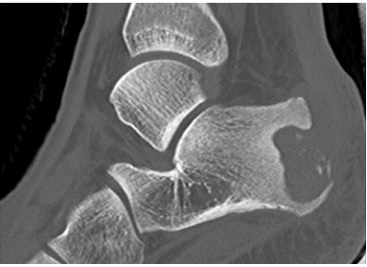

La radiografía convencional fue examen de rutina en todos los pacientes del estudio. Evidenció hallazgos inespecíficos en 5 de 9 pacientes consistentes en edema de tejidos blandos. En uno de esos casos se apreciaron lesiones óseas en el calcáneo (Figura 1). La TC se utilizó como complemento en un caso para confirmar un defecto óseo cortical secundario a la infección (Figura 2).